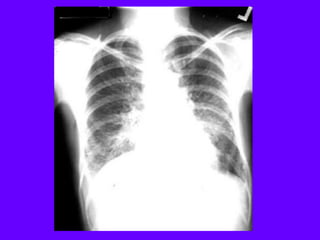

Upper lobe Bulla